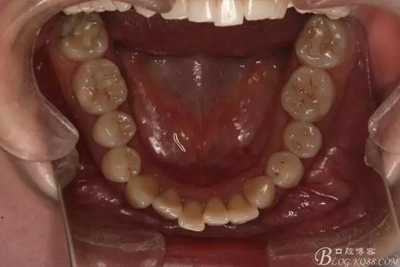

患者,女,主訴:牙齒不齊。

如圖,該病例為簡單排齊病例,但77鎖合是矯治中的關(guān)鍵所在,你會怎么處理?

該病例主要為17、27頰側(cè)位同時伴有伸長,當然種植支抗可以解決,但還有簡單實用的辦法嗎?如圖,在橫腭桿遠中延伸出牽引鉤,位置盡量遠離合平面,7粘舌側(cè)扣,牽引力的方向為壓低及舌向,下圖為兩個月的效果,17已到位,27還未到位。